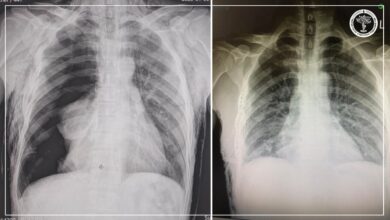

УГТЭ уналт таталтын мэс заслыг бие даан хийж эхэллээ

Манай улсад эпилепси буюу унаж татах эмгэгийн оноштой хүмүүст өнөөдрийг хүртэл зөвхөн эмийн эмчилгээ хийгдэж ирсэн бол Улсын гуравдугаар төв…